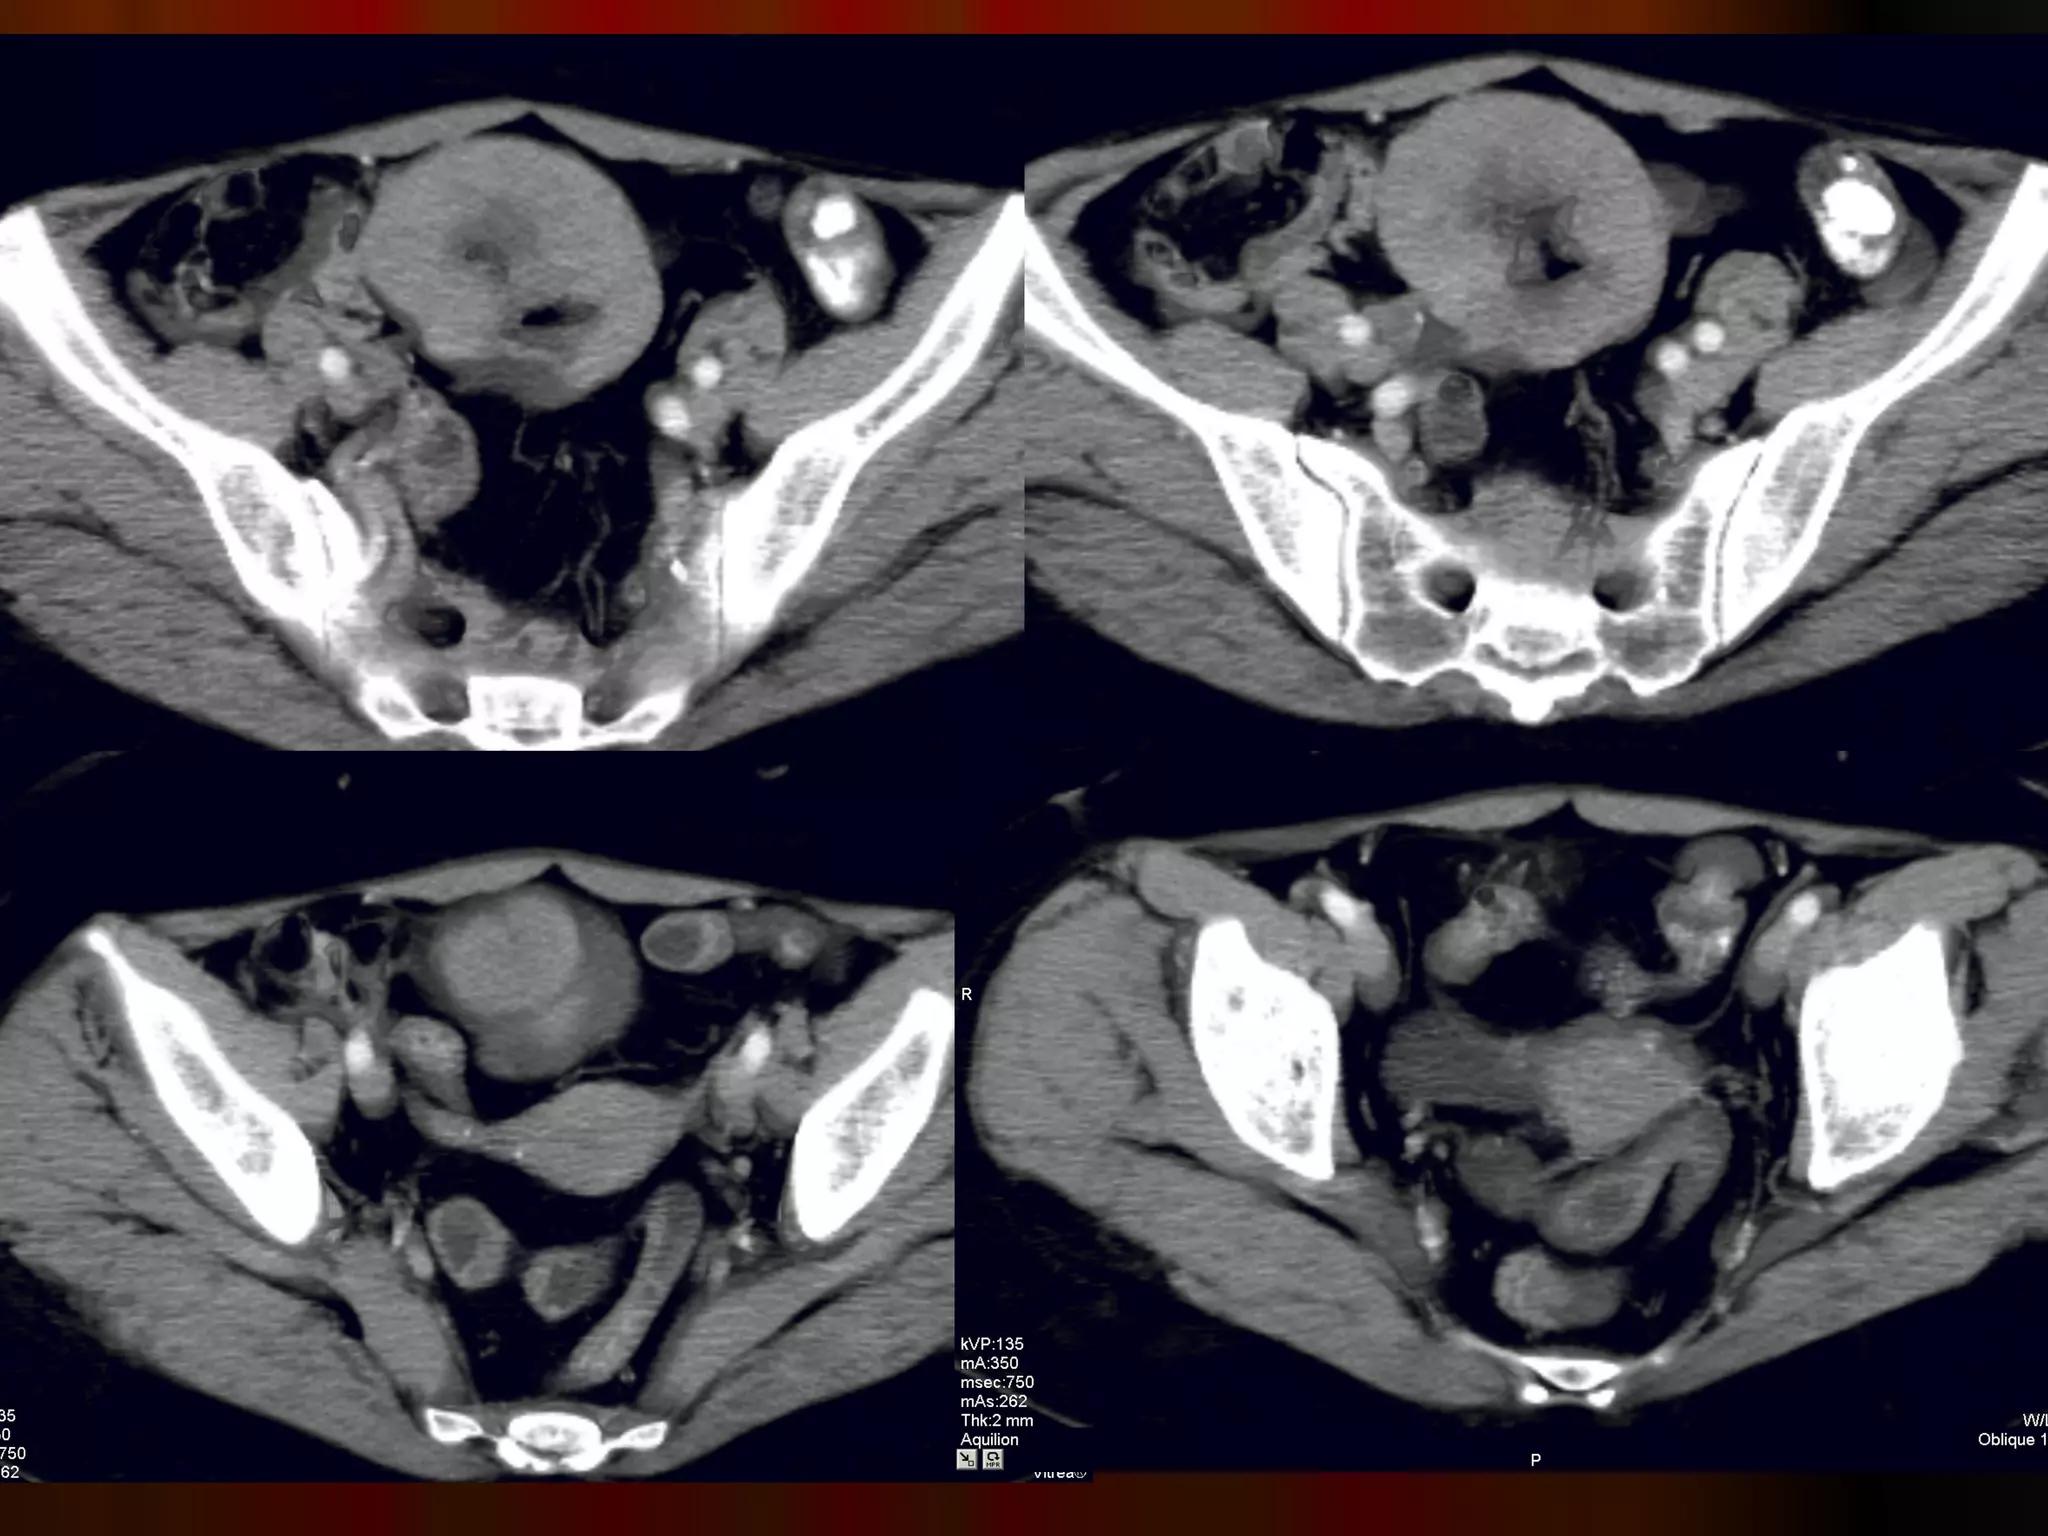

Женщина, 70 лет,боли в эпигастрии, анемия, резкая потеря веса Случай 4.

Инфильтративная форма ракажелудка с региональным прорастанием, метастазы в яичники ( рак Крукенберга) и параректальную клетчатку ( Шницлеровский метастаз)

Женщина, 70 лет, боли в эпигастрии, анемия, резкая потеря веса Случай 4.

Инфильтративная форма рака желудка с региональным прорастанием, метастазы в яичники ( рак Крукенберга) и параректальную клетчатку ( Шницлеровский метастаз)